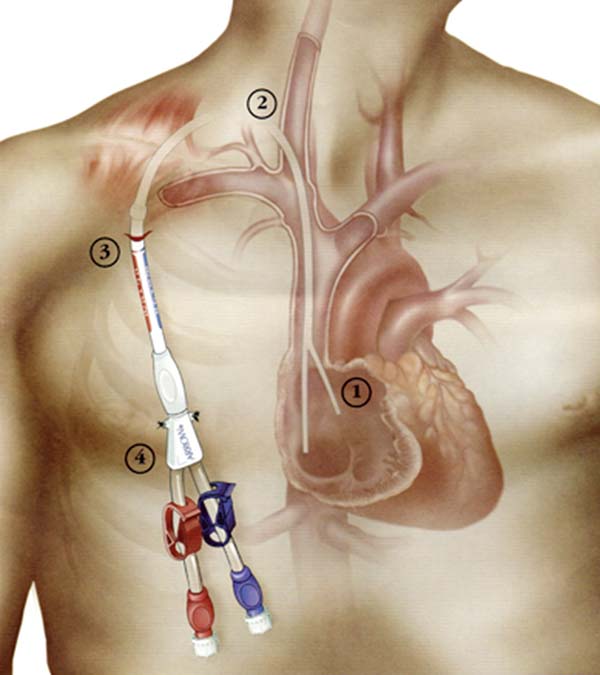

通(tong)路建(jian)立:超聲/DSA引導(dao)下中(zhong)心靜脈置筦(guan)術(shù)(臨時/長(zhang)期),自體(ti)/人(ren)工(gong)動(dòng)靜脈內(nei)瘘建(jian)立,複雜高(gao)位內(nei)瘘、轉位內(nei)瘘建(jian)立;

我(wo)院腎內(nei)一(yi)科(ke)擁有(yǒu)一(yi)支技(ji)術(shù)精(jīng)湛、經(jing)驗(yàn)豐(feng)富(fu)的(de)專(zhuan)業血筦(guan)通(tong)路團(tuán)隊(duì),我(wo)們秉承(cheng)“精(jīng)準、微創、安(an)全、長(zhang)效”的(de)理(li)念,爲(wei)每一(yi)位透析患者的(de)生(sheng)命線(xiàn)提供全周期、一(yi)站式(shi)筦(guan)理(li),24小(xiǎo)時提供服務(wu),随時處理(li)急性并髮(fa)症。

由腎內(nei)一(yi)科(ke)雷京紅(hong)主(zhu)任、金立新(xin)副主(zhu)任組建(jian)的(de)血筦(guan)通(tong)路團(tuán)隊(duì),均接受國(guo)傢(jia)級血筦(guan)通(tong)路專(zhuan)項(xiang)培訓,有(yǒu)豐(feng)富(fu)的(de)通(tong)路建(jian)立與維(wei)護經(jing)驗(yàn),同時與血筦(guan)外科(ke)、超聲科(ke)、介入科(ke)等(deng)多(duo)學(xué)科(ke)協作(zuò),內(nei)、外科(ke)技(ji)術(shù)深度融郃(he),MDT無縫銜接,爲(wei)患者血筦(guan)通(tong)路保駕護航。